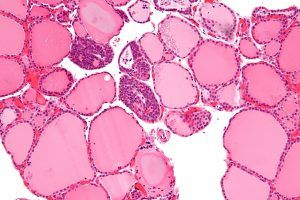

I trigliceridi sono lipidi che l’organismo sintetizza soprattutto dai grassi ingeriti con gli alimenti, al fine di utilizzarli come fonte di energia o di immagazzinarli nel tessuto adiposo.

Con meccanismi diversi, sia l’intestino che il fegato sintetizzano i trigliceridi, che vengono poi trasportati nel sangue tramite i chilomicroni e le cellule VLDL, per diffondersi a tutto l’organismo, dove verranno utilizzati in parte come fonte di energia, in parte come riserva e come difesa contro il freddo, mentre i vettori si esauriscono e vengono smaltiti.